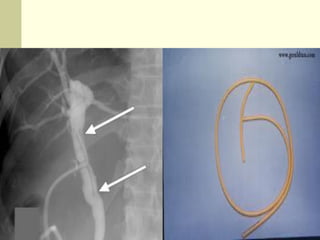

C-2- Condom Catheter

C-3 Double J Catheter

C-4- Nephrostomy Tubes

Malecot

Pigtail